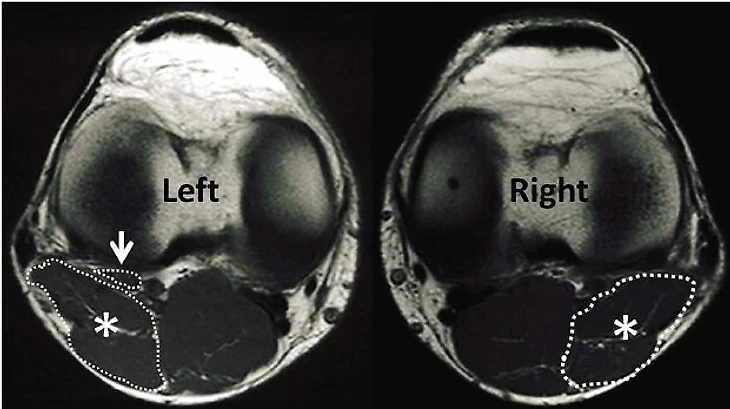

Вот, например, картинка из исследования турецких специалистов, где взяли срез МРТ 2 коленных суставов, где мы смотрим на них как бы сверху. Вверху это надколенник, коленная чашечка, снизу икроножная мышца. Что мы видим под стрелочкой? Слева мышца есть, а справа уже нет. То есть, чтобы поставить этот диагноз мышцу надо еще найти.